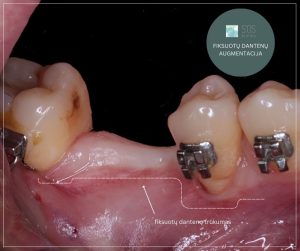

Fiksuotų dantenų trūkumas

Kai fiksuotų dantenų trūksta, aplink dantį ar implantą lengviau kaupiasi bakterijos, nes paslanki gleivinė neužtikrina stabilaus barjero tarp dantenų ir implanto, todėl dantenų vagelėje gali kauptis apnašas. didėja dantenų uždegimo ir dantenų atsitraukimo rizika, o kasdienė burnos higiena tampa sudėtingesnė ir mažiau efektyvi.